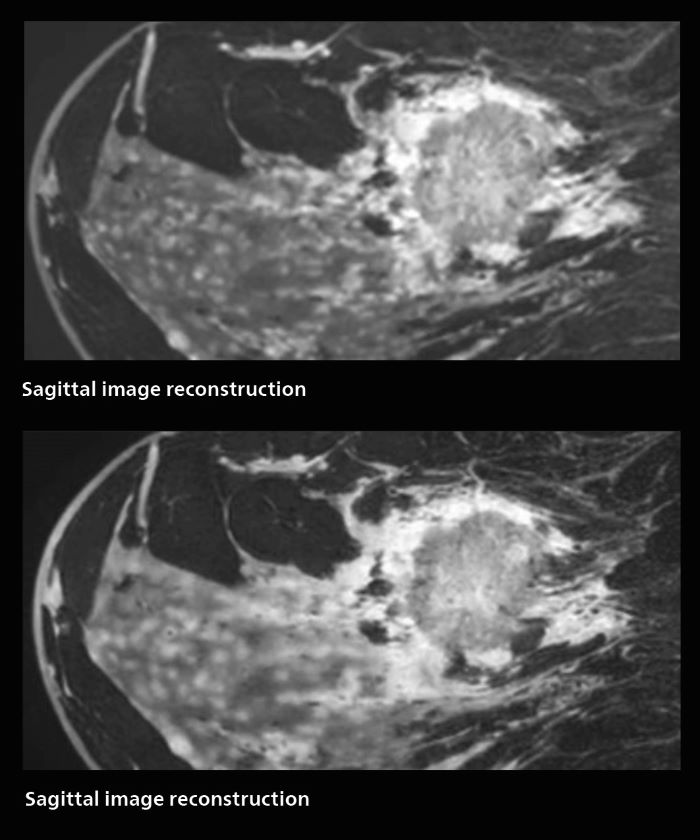

MRI of rectal cancer

In this patient MRI was done to help in diagnosing the depth of invasion. Performed on Elition X.

MRI of rectal cancer: fast isotropic 3D acquisitions providing excellent image quality with use of AI-enabled SmartSpeed

The hospital’s routine ExamCard for rectal cancer includes:

• T2 VISTA, 4.59 min, 0.75 mm isotropic, acceleration factor 12

• Dyn mDIXON TFE, 2.33 min, 12.5 sec/dynamic, 1.2 x 1.2 x 4.4 mm, acceleration factor 3

• DWI EPICS b1000, 5.06 min, 2.0 mm isotropic, acceleration factor 2.5